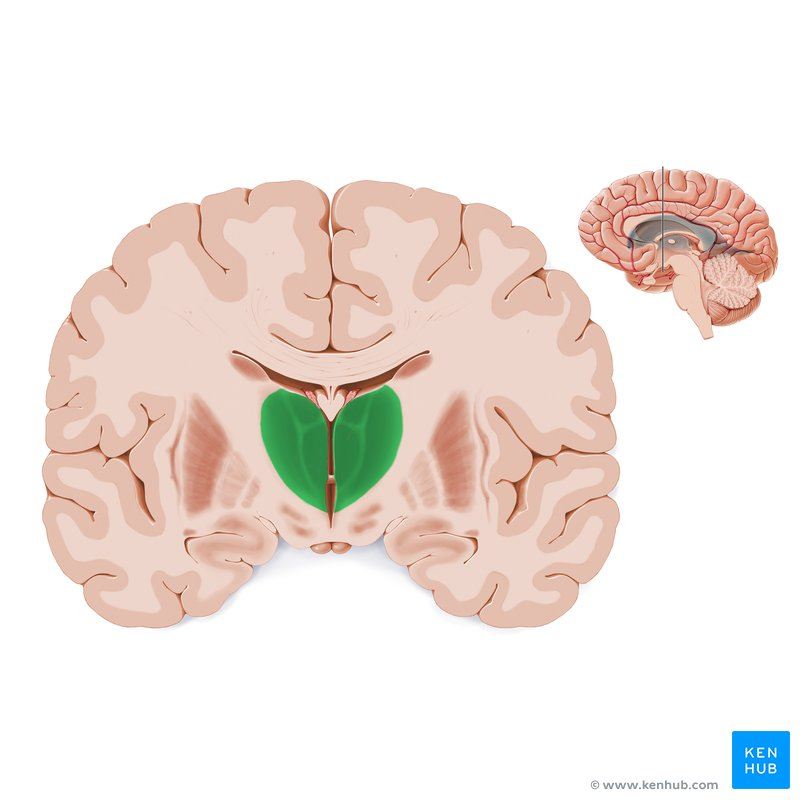

Many researchers believe that the entire brain is involved with memory, in some way or another (Lashley, 1950). However, some key areas have been identified (shown below in Figure 1.) and include the amygdala, hippocampus, cerebellum, the prefrontal cortex and the synapses linking them all (Mayford, Siegelbaum, & Kandel, 2012).